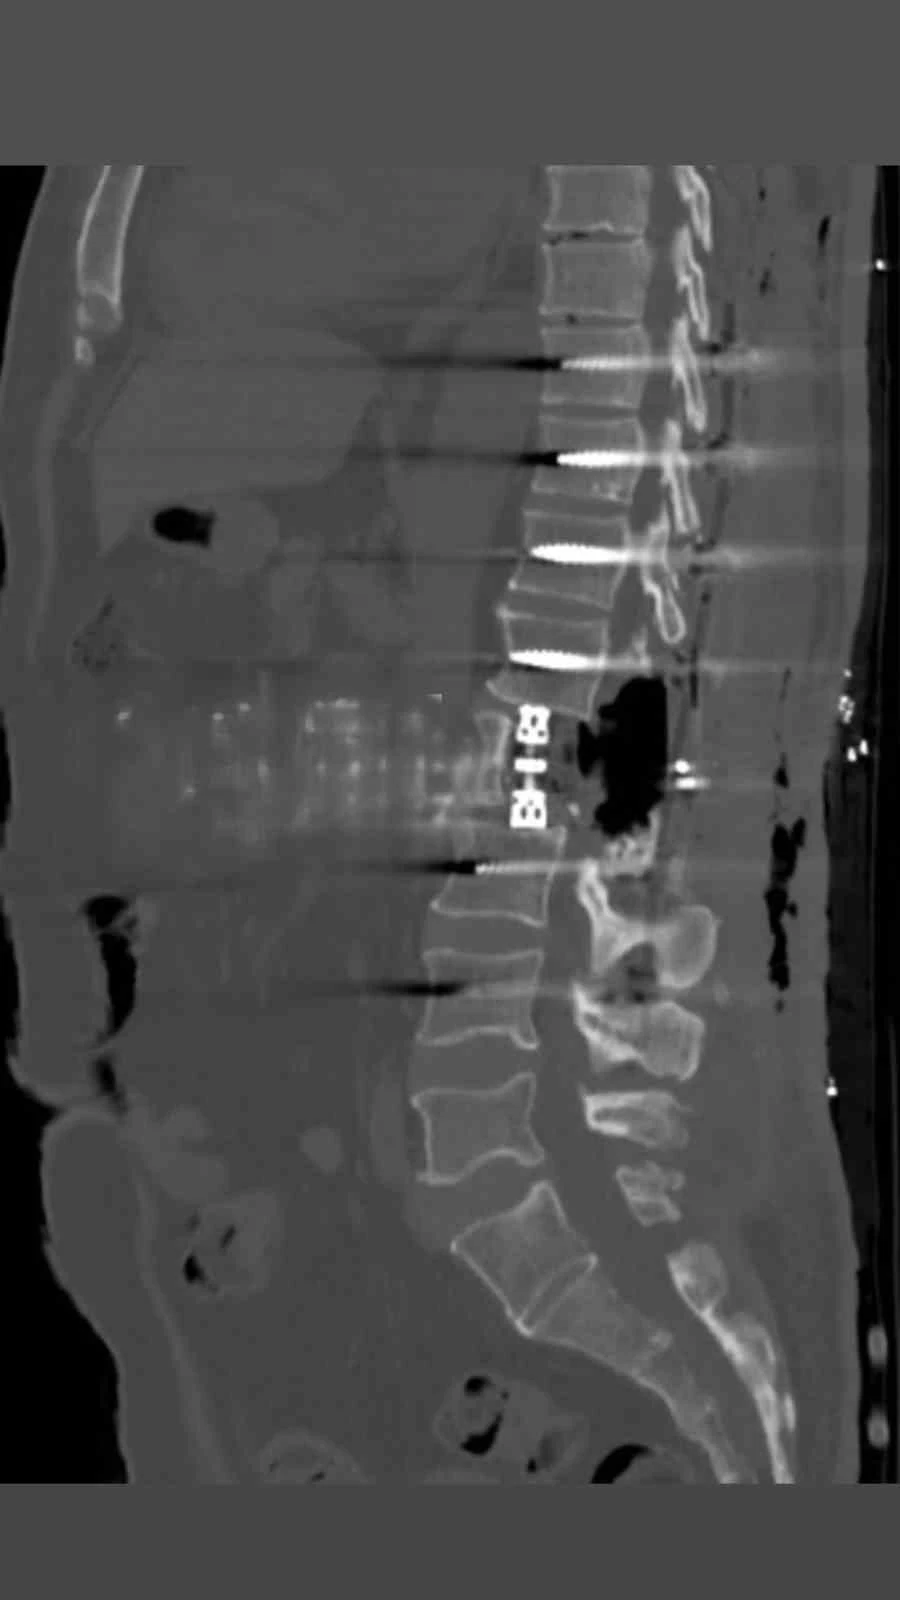

Bayburt Devlet Hastanesinde omurga bölgesindeki tümörler yapılan korpektomi işlemiyle alındı. Omurganın bir kısmının cerrahi olarak çıkarılması işlemi olan korpektomi ameliyatı Op.Dr Aziz Kaan Erçandırlı ve Op.Dr Ali Emre Özer tarafından başarılı bir şekilde yapıldı.

Bayburt Devlet Hastanesine belli başlı şikayetlerle başvuran hastaya korpektomi ameliyatı yapılarak, hastanın tümörleri temizlendi. Hastanın bel omurundaki enfeksiyon temizlendikten sonra kafes ve enstrüman sistemi ile sabitleme yapıldı. Beyin ve Sinir Cerrahisi Uzmanları Op.Dr Aziz Kaan Erçandırlı ve Op.Dr Ali Emre Özer tarafından yapılan operasyonla, hasta sağlığına kavuştu.